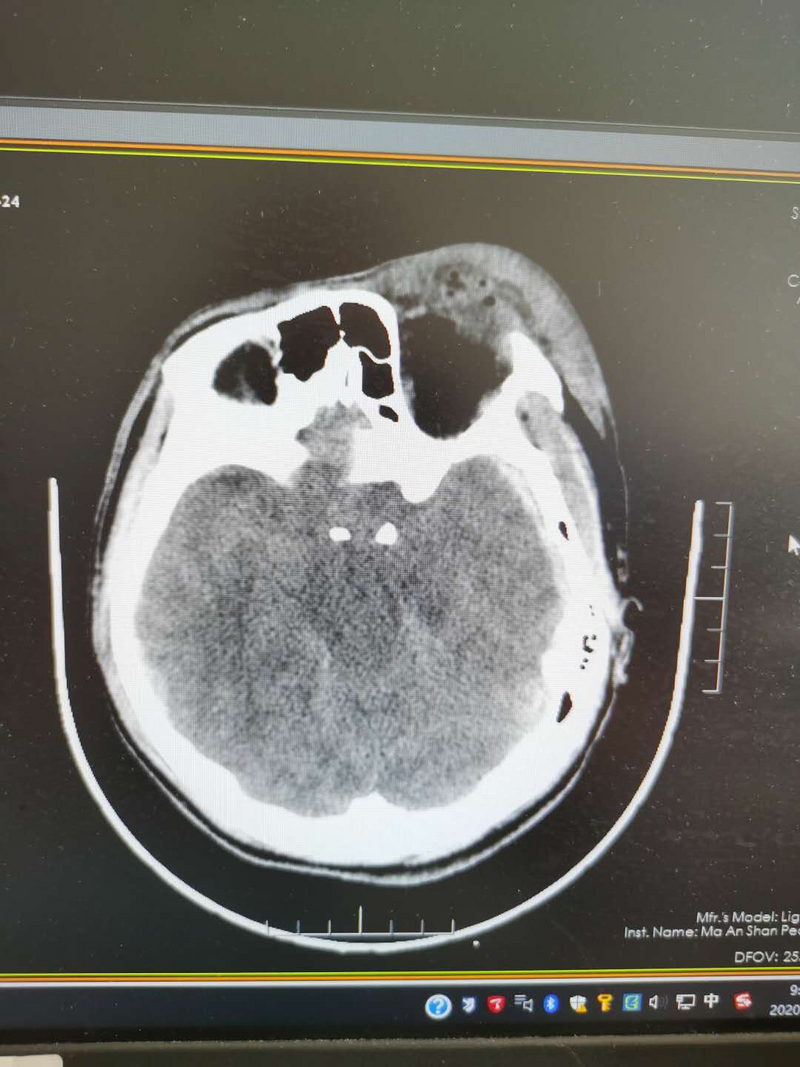

8月19日上午,年僅21歲的山西小伙趙某工作時不慎從8米高處摔下,頭部著地,當(dāng)即昏迷。趙某同事立即撥打120送入我院救治?;颊呷朐簳r深度昏迷,雙側(cè)瞳孔散大,呼吸微弱,生命垂危。CT檢查證實(shí)患者特重型顱腦損傷、廣泛性硬膜下血腫、顱骨粉碎性骨折、多發(fā)肋骨骨折伴氣胸。

患者頭顱CT示廣泛性顱腦損傷,環(huán)池消失,腦干受壓、中線移位。查體:GCS3分(最低分)深度昏迷,雙側(cè)瞳孔散大,呼吸微弱,生命垂危。